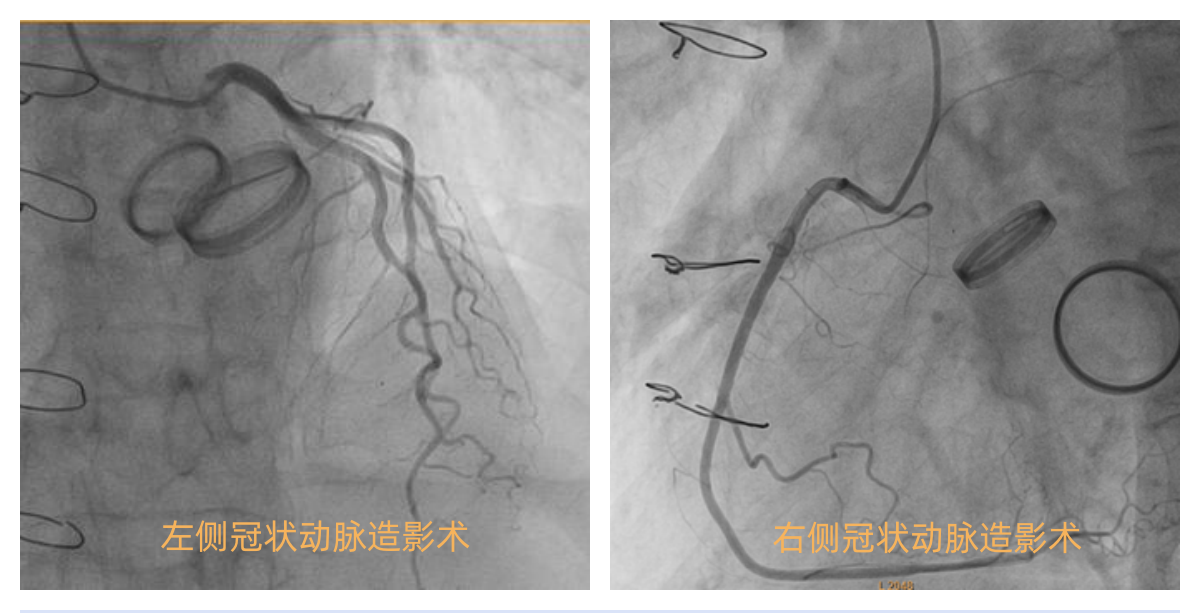

术前请心血管内科协助评估患者冠脉情况,组织术前讨论,考虑患者为二次手术及右心功能不全,手术创伤大、难度高、风险大、出血多、术后恢复困难,与相关科室组织MDT讨论围手术期诊疗方案,为突发紧急情况做好全面预案。